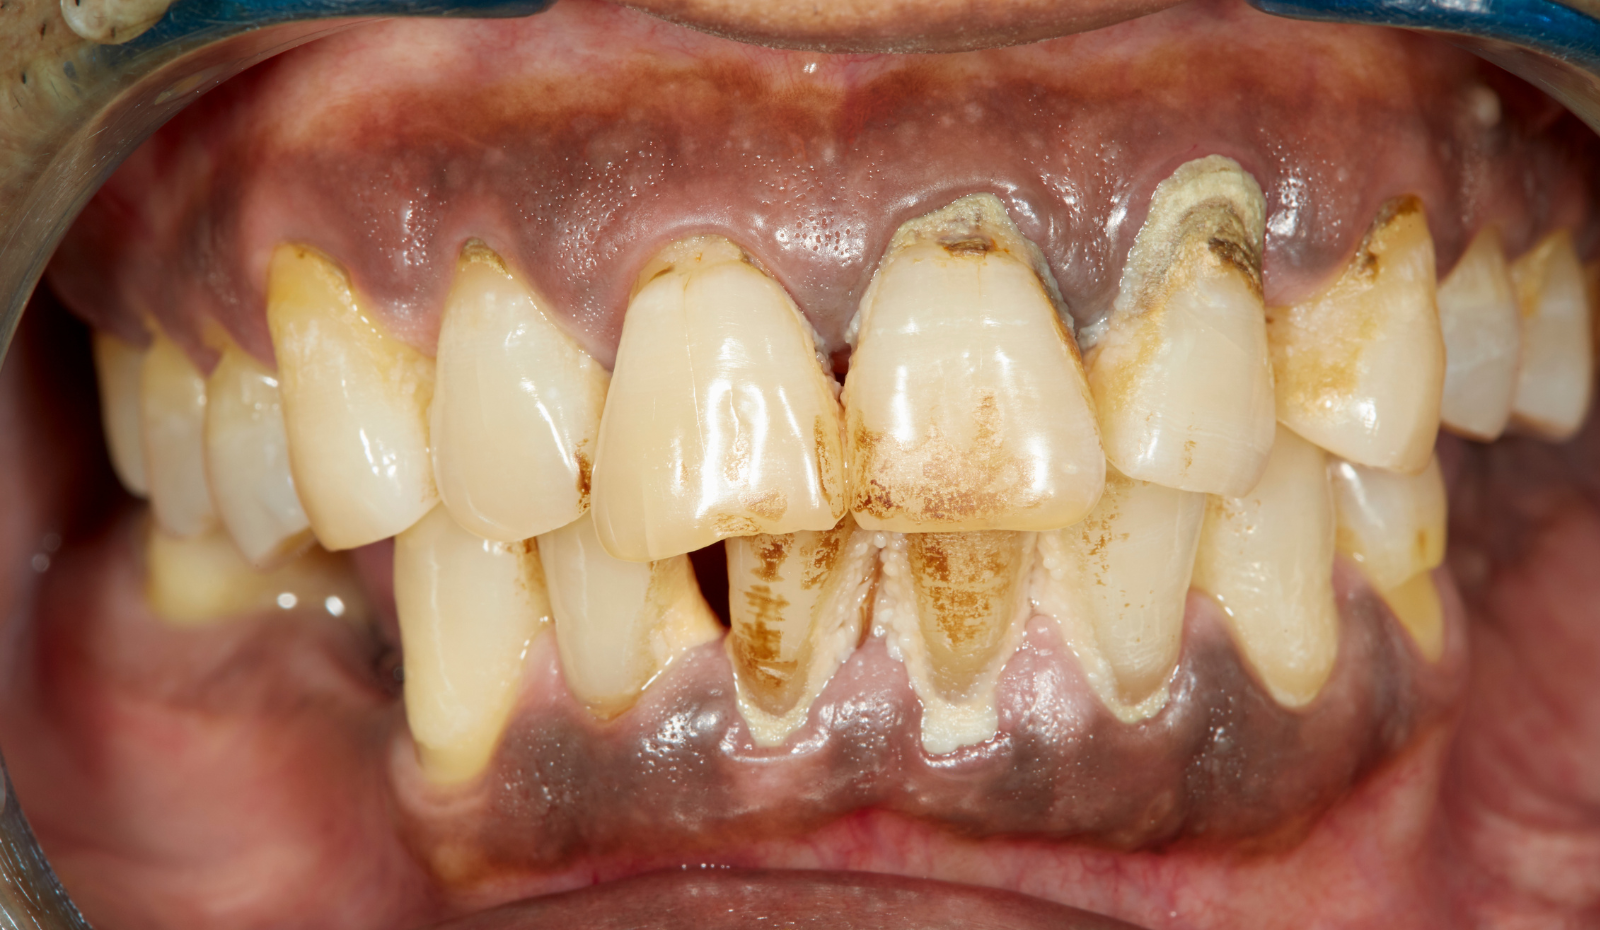

Periodontal pockets rarely announce their presence with acute, unmistakable pain, which contributes significantly to the prevalence of undiagnosed or late-stage periodontitis. Instead, they present with subtle, chronic signs that are often dismissed by the patient. Common indicators include persistent bad breath (halitosis) resulting from the anaerobic bacterial activity within the pocket, a persistent metallic or unpleasant taste, bleeding gums, especially during brushing or flossing, and a noticeable recession of the gumline, making the teeth appear longer. In advanced stages, patients may observe a loosening or splaying of their teeth, changes in the way their teeth fit together (malocclusion), or the presence of pus exuding from the gum margin.

The definitive diagnosis and measurement of periodontal pockets are performed by a dental professional using a specialized instrument called a calibrated periodontal probe. This probe is gently inserted into the sulcus or pocket parallel to the long axis of the tooth until a firm resistance is met, which corresponds to the base of the junctional epithelium. The depth is read directly from the markings on the probe. A full-mouth periodontal charting records these measurements for every tooth at six different sites, providing a comprehensive map of the disease progression. In addition to probing depths, clinical attachment loss (CAL), which is the true measure of tissue destruction calculated from a fixed reference point, must also be assessed. Radiographs (X-rays) are also essential to visualize and quantify the extent and pattern of alveolar bone loss, complementing the soft-tissue measurements.